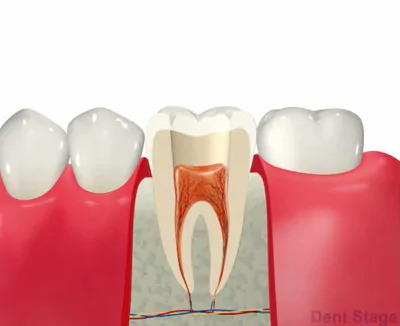

根管治療とは、いわゆる「歯の神経の治療」のことです。

むし歯が深くまで進んで神経にまで達してしまった場合に行う治療で、歯の根の中をきれいに掃除して、ばい菌が入らないように薬を詰めて密閉します。歯の根っこの内部には、神経や血管が入っています。ここを根管と言います。

むし歯が進行して、根の中に菌が入ると汚れがたまります。汚れている根管を綺麗にするために、ファイルという器具で掃除し、消毒薬を使って汚れを洗い流し、治療と治療の間で菌を増やさない様に薬を詰めます。最終的に根管が綺麗になったら、細菌が繁殖しない様にお薬を詰めて終わりになります。この治療をしっかり行う事により、患者様の歯を更に長生きさせることができます。